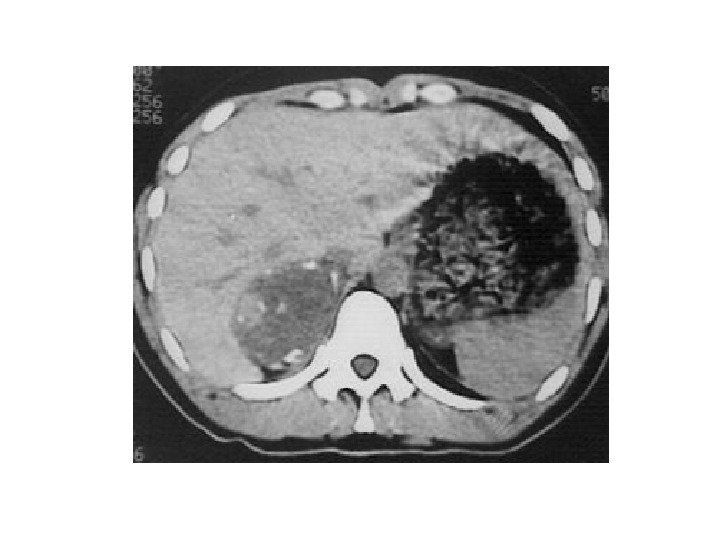

• В 10% случаев при феохромоцитоме компьютерная томография выявляет двустороннее поражение надпочечников. • Билатеральная феохромоцитома часто проявляется как незначительное увеличение надпочечников, с заметным повышением их васкуляризации. • Необходимо помнить, что феохромоцитома может иметь и вненадпочечниковую локализацию, располагаясь в паракавальных симпатических ганглиях, симпатических ганглиях средостения, ганглиях стенки мочевого пузыря.

• В 10% случаев при феохромоцитоме компьютерная томография выявляет двустороннее поражение надпочечников. • Билатеральная феохромоцитома часто проявляется как незначительное увеличение надпочечников, с заметным повышением их васкуляризации. • Необходимо помнить, что феохромоцитома может иметь и вненадпочечниковую локализацию, располагаясь в паракавальных симпатических ганглиях, симпатических ганглиях средостения, ганглиях стенки мочевого пузыря.